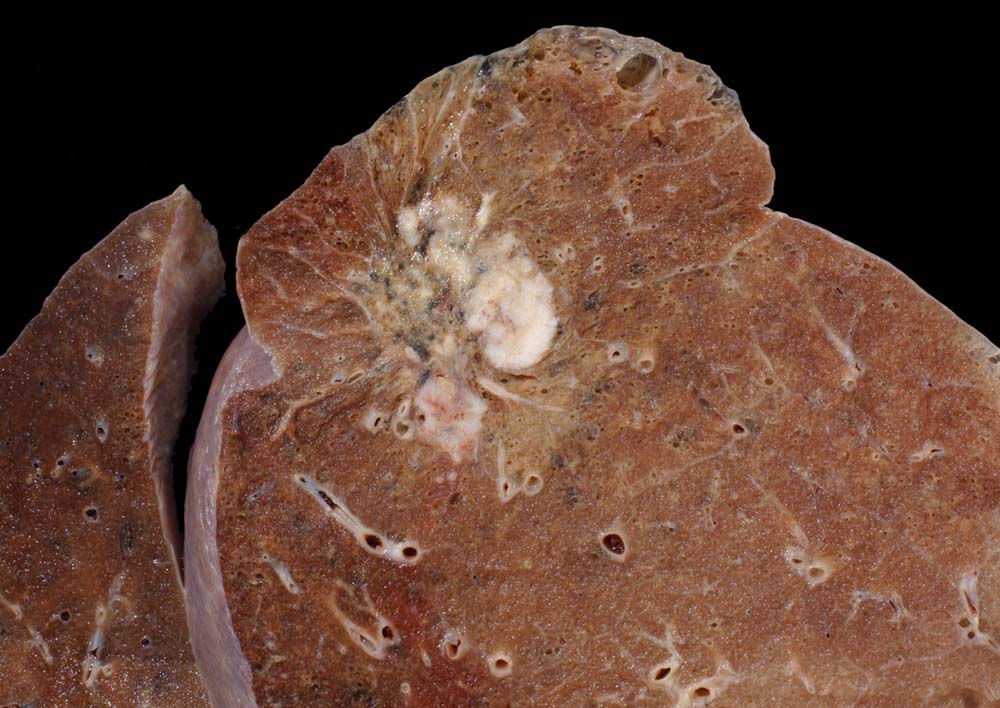

Makroskopie

Befund

Pathologischer Befund